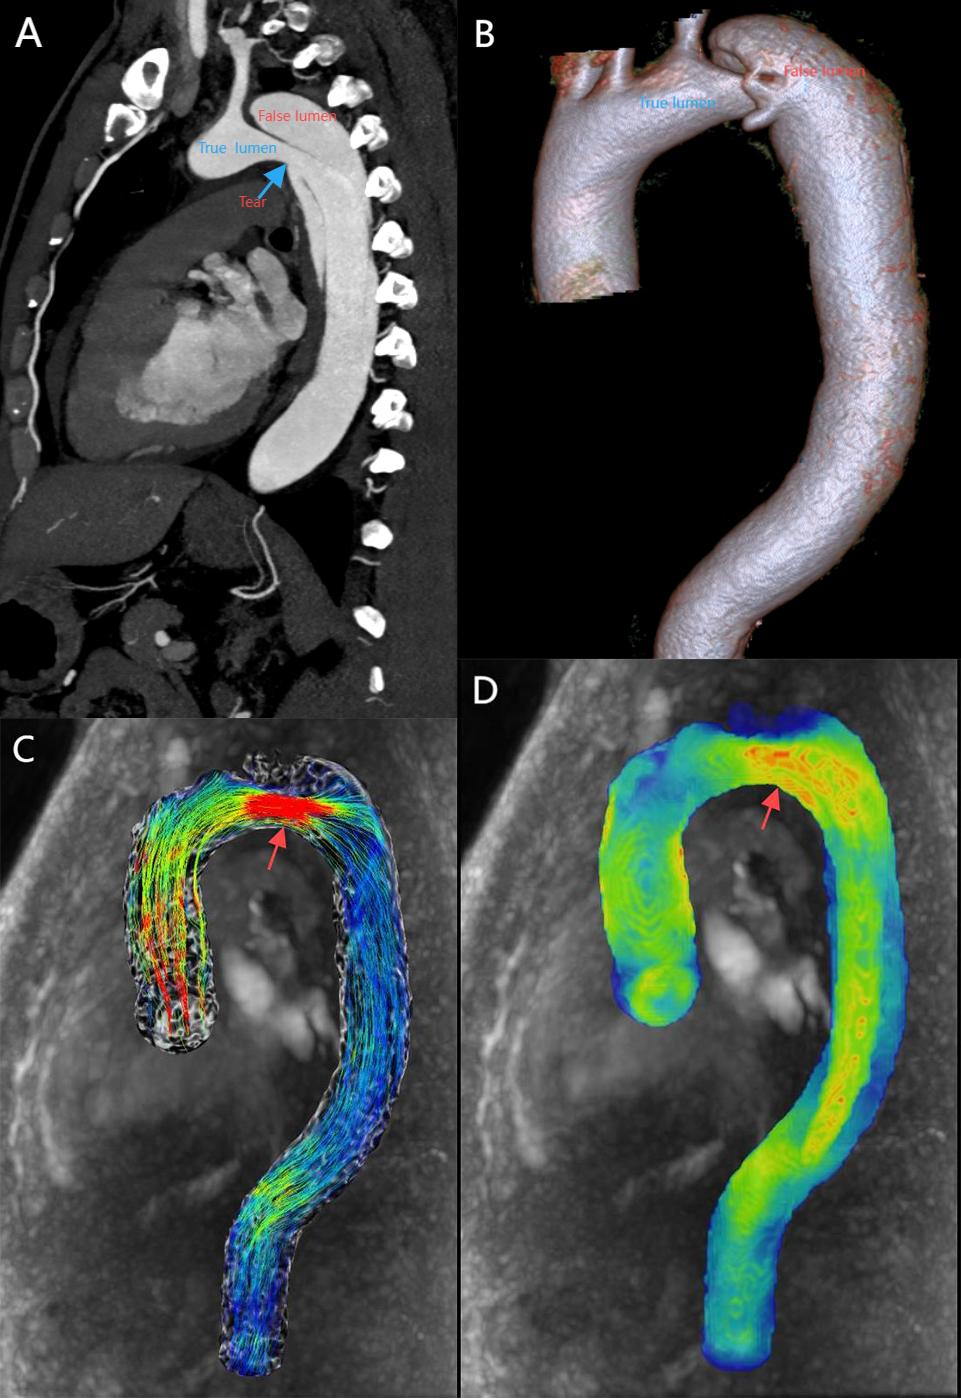

Aortic dissection is one of the common types of acute aortic syndrome (AAS) with rapid onset and high mortality. Early screening for the potential risk of aortic dissection in high-risk groups would facilitate clinical preventive measures and reduce patient mortality. Fig. 3 shows aortic dissection evaluated by imaging modalities. Research has found that the area of highest WSS is highly coincident with the location of the tear in stanford type A aortic dissection [70]. This suggests that increased WSS may be an important factor in endovascular injury. Patients with stanford type B aortic dissection can be treated medically or surgically based on clinical assessment, and real-time monitoring of the dynamic evolution of the aortic dissection is mandatory. Increased aortic diameter and partial thrombosis of the false lumen are associated with late adverse events in type B aortic dissection [71, 72]. WSS may be a good indicator for monitoring these changes. On the one hand, WSS is positively correlated with the aortic growth rate [27], which could be used as a predictor of the distant expansion of aortic dissection. On the other hand, low WSS, high RRT, flow patterns are correlated with thrombosis [73]. There is increasing evidence to indicate that 4D flow MRI-based hemodynamics plays an important role in aortic dissection management and prognosis [27, 28, 29, 74].

Fig. 3. A patient with stanford type B aortic dissection. (A) 2D sagittal view, showing true and false lumen as well as entry tear (blue arrow). (B) 3D VR displays true lumen, false lumen. (C) 4D-flow-Image with streamlines demonstrates high velocity at the entry tear (red arrow). (D) 4D-flow-Image demonstrates high WSS at the entry tear (red arrow). 2D, two dimensions; 3D, three dimensions; VR, volume rendering.